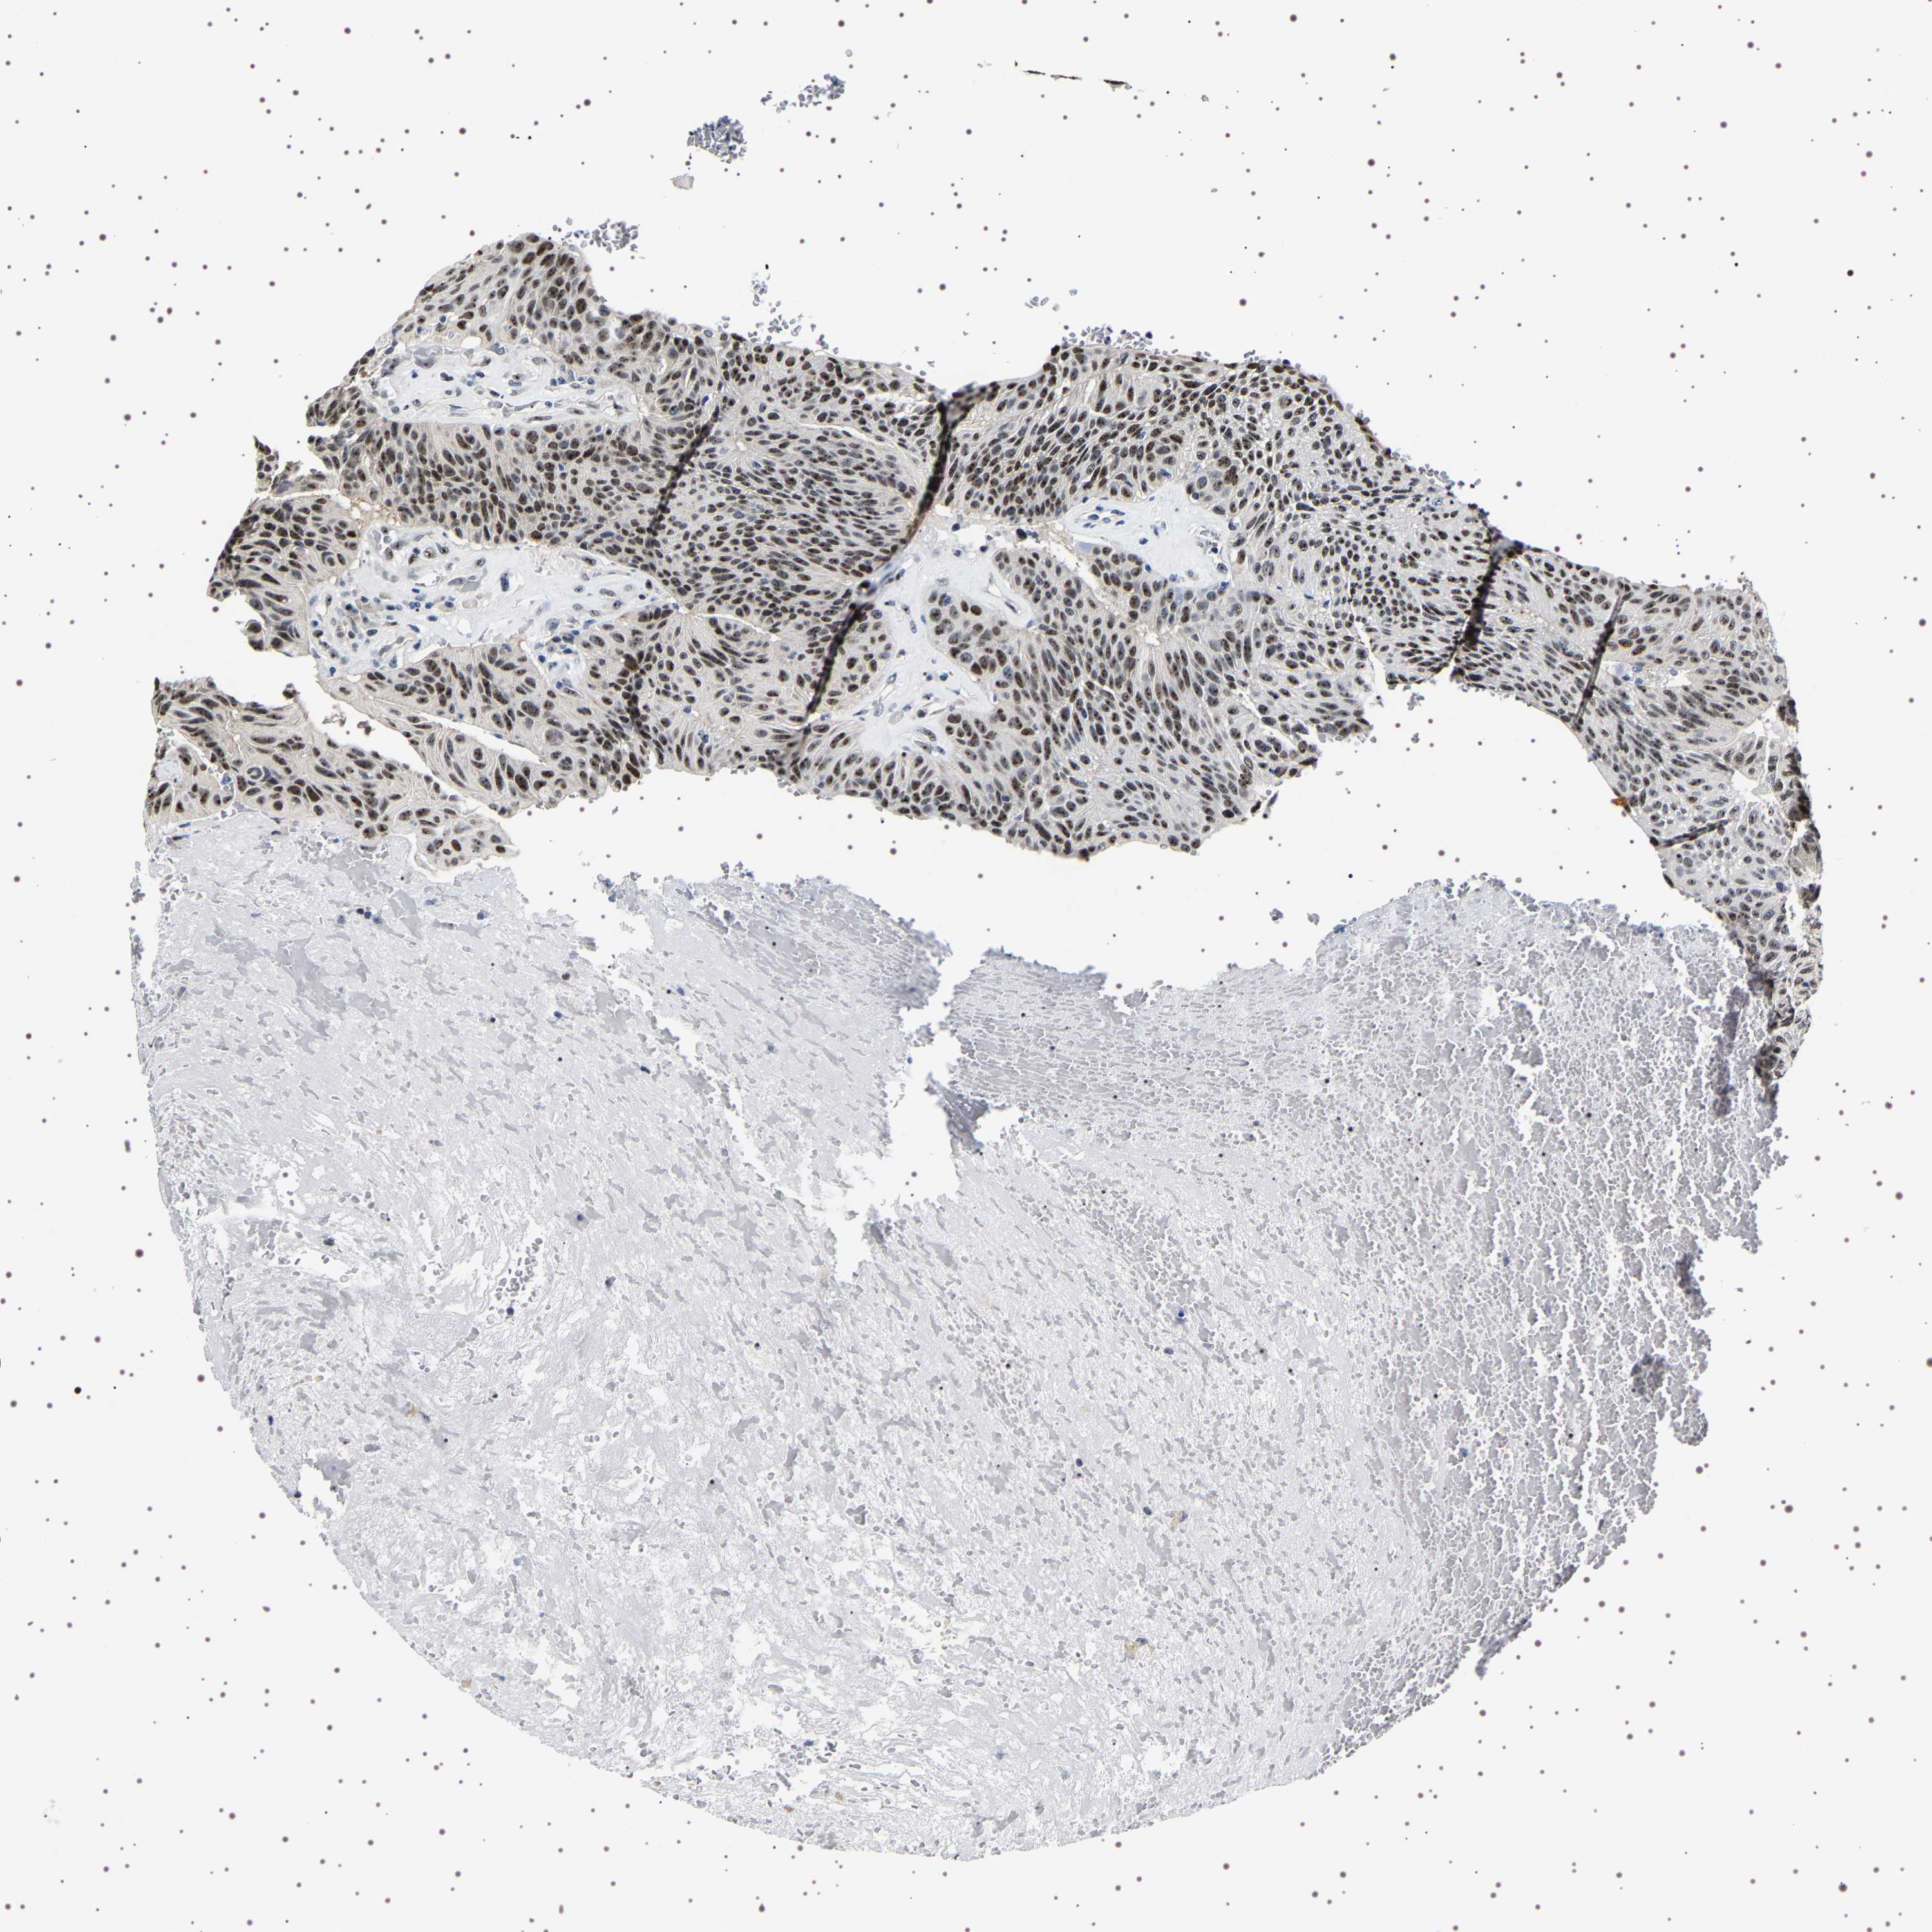

UROTHELIAL CANCER - Protein expressioni

A mouse-over function shows sample information and annotation data. Click on an image to view it in a full screen mode. Samples can be filtered based on level of antibody staining by selecting one or several of the following categories: high, medium, low and not detected. The assay and annotation is described here.

Note that samples used for immunohistochemistry by the Human Protein Atlas do not correspond to samples in the TCGA dataset.

Antibody stainingi

Antibody staining in the annotated cell types in the current human tissue is reported as not detected, low, medium, or high, based on conventional immunohistochemistry profiling in selected tissues. This score is based on the combination of the staining intensity and fraction of stained cells.

Each image is clickable and will lead to virtual microscopy that enables deeper exploration of all samples and also displays staining intensity scores, fraction scores and subcellular localization as well as patient and tissue information for each sample.

Antibody HPA036742

Antibody HPA036743

Antibody CAB020770

Staining

High

Medium

Low

Not detected

Intensity

Strong

Moderate

Weak

Negative

Quantity

>75%

75%-25%

<25%

None

Location

Nuclear

Cytoplasmic/membranous

Cytoplasmic/membranous,nuclear

Urothelial carcinoma, High grade

Urothelial carcinoma, Low grade